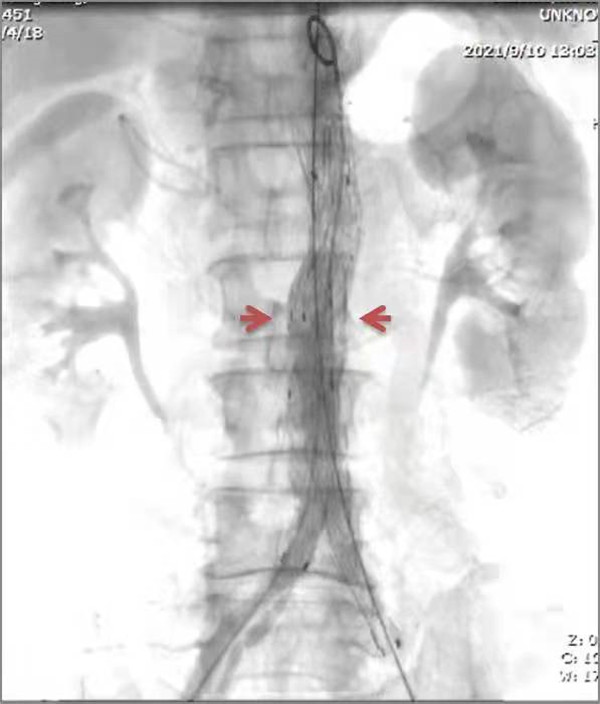

術後

由於患者高齡、基礎疾病較多,如同時行兩種手術,存在較高風險,但病人強烈希望能夠一起解決這兩個問題,經全面評估考慮,周偉忠主任決定兩種疾病同時處理,行微創腔內治療。術前詳細測定患者病變段血管數據,制定了周詳的手術方案,在周偉忠主任帶領下,瞿鵬、劉焱喆醫生及麻醉醫生、導管室配合下實施手術。藝高人膽大,術中,周偉忠主任團隊於主動脈放置覆膜支架隔絕腹主動脈瘤,腸繫膜上動脈支架植入使腸繫膜上動脈血流恢復。手術順利完成。術後患者恢復良好,術後三天即下地活動,患者腹痛、腹脹症狀消失,一周後出院。

據周偉忠主任介紹,腹主動脈瘤腔內覆膜支架隔絕術(EVAR)是近年來治療腹主動脈瘤的微創手術方式,其特點是創傷小,避免了傳統手術所帶來的巨大創傷和痛苦,降低了病人心、肺等重要臟器併發症的發生率和死亡率,尤其對於一些有嚴重合併症、預期不能耐受傳統開腹手術或手術後可能出現嚴重併發症的高危病例提供了治療的機會。腸繫膜上動脈狹窄所引起腹部症狀常常並不典型,容易和其他腹部疾病混淆,所以診斷難度較大,需要臨床醫生有豐富的臨床經驗。腹主動脈瘤合併腸繫膜上動脈狹窄患者臨床少見,兩種疾病同時治療手術難度極高,這次手術的成功開展挽救了患者的生命,展現了百年市一院多學科MDT團隊的良好協作,也體現了市一院周圍血管外科的手術領域、手術水平和技術邁上了新台階。(裴振萍 江麗波 瞿鵬 劉焱喆 張曉磊)